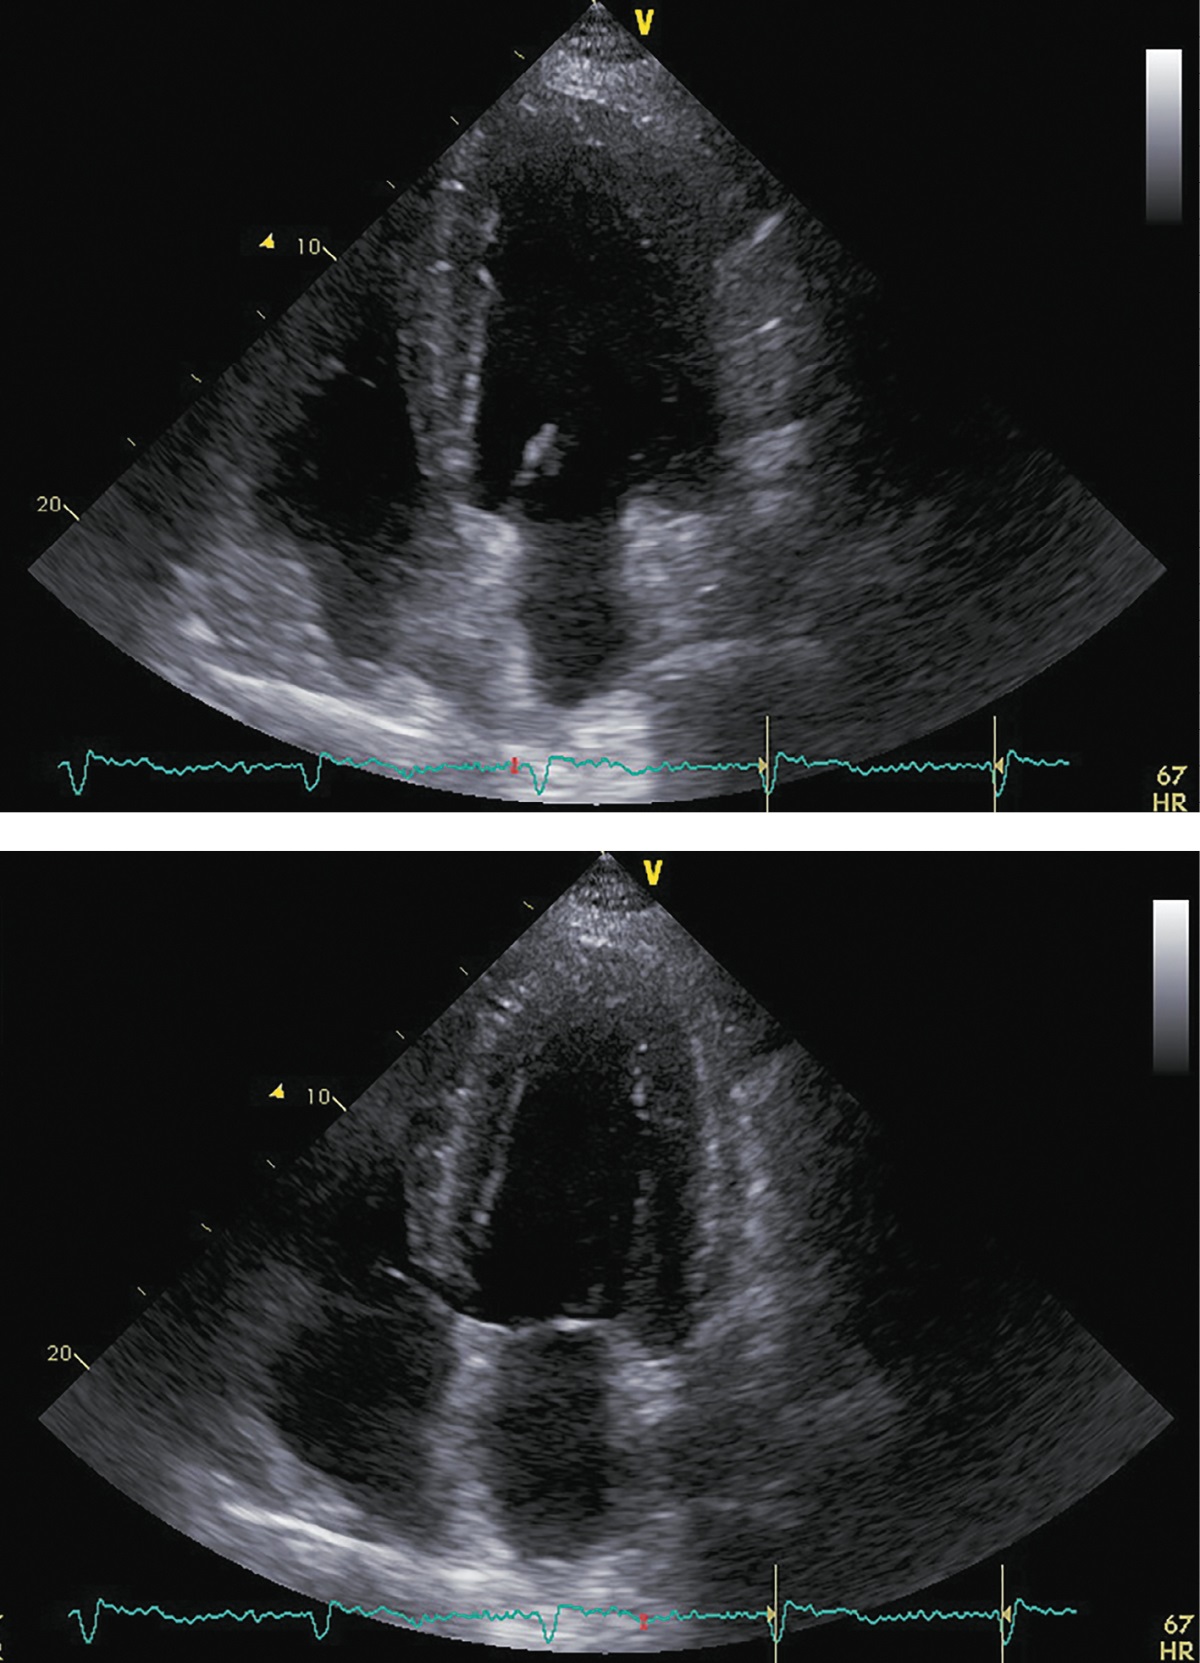

При последующих госпитализациях для динамического наблюдения (май 2018 г.; декабрь 2018 г.; декабрь 2019 г.) состояние пациента соответствовало стабильной клинической ремиссии. Заместительная терапия была отменена в декабре 2018 г., в дальнейшем показатели секреции кортизола находились в пределах референсных значений (табл. 1). Толерантность к физическим нагрузкам оставалась на уровне II ф.к. по NYHA. Физикальная симптоматика, характерная для ХСН, отсутствовала. При проведении контрольных ЭХОКГ-исследований отмечалось дальнейшее уменьшение размеров и объемов левого желудочка со стабилизацией ФВ ЛЖ на субнормальном уровне (рис. 6, 7, 8; табл. 4, 5, 6 соответственно). В связи с сохраняющейся АГ поликомпонентная гипотензивная терапия была продолжена в том же объеме с добавлением к ней альфа-адреноблокатора (доксазозин 2 мг два раза в сутки). СД контролировался метформином с достижением целевого уровня гликемии и гликированного гемоглобина. Уровень креатинина оставался стабильным, значимой динамики СКФ обнаружено не было (табл. 7).

Рисунок 6. ЭХОКГ через 6 месяцев после аденомэктомии.

Примечание: верхушечная 4-камерная позиция (сверху представлен кадр в диастолу, снизу — в систолу).

Рисунок 7. ЭХОКГ через 12 месяцев после аденомэктомии.

Примечание: верхушечная 4-камерная позиция (сверху представлен кадр в диастолу, справа — в систолу.

Рисунок 8. ЭХОКГ через 24 месяца после аденомэктомии.

Примечание: верхушечная 4-камерная позиция (сверху представлен кадр в диастолу, справа — в систолу).

Таблица 4. ЭХОКГ-показатели через 6 месяцев после аденомэктомии

|

Показатель |

Значение/индекс |

Объем левого предсердия |

77 мл/33 мл/м² |

Передне-задний размер левого желудочка |

6,10 см/2,44 см/м² |

Конечно-диастолический объем левого желудочка |

211 мл/91 мл/м² |

Конечно-систолический объем левого желудочка |

103 мл/44 мл/м² |

Локальная кинетика левого желудочка |

Нормальная кинетика |

Фракция выброса левого желудочка (усреднение по 4- и 2-камерным верхушечным позициям) |

51% |

Диастолическая функция левого желудочка |

градация II, псевдо-нормальный тип |

Конечно-диастолическая площадь правого желудочка |

25,5 см²/10,9 см²/м² |

Конечно-систолическая площадь правого желудочка |

14,8 см²/6,4 см/м² |

Фракция систолического уменьшения площади |

41% |

Расчетное систолическое давление в легочной артерии |

41 мм рт.ст. |

Таблица 5. ЭХОКГ-показатели через 12 месяцев после аденомэктомии

81 мл/34 мл/м² |

5,2 см/2,08 см/м² |

174 мл/74 мл/м² |

90 мл/38 мл/м² |

49% |

градация I, нарушения релаксации |

22,9 см²/9,8 см²/м² |

11,2 см²/4,8 см/м² |

48 мм рт.ст. |

Таблица 6. ЭХОКГ-показатели через 24 месяца после аденомэктомии

97 мл/41 мл/м² |

5,2 см/2,19 см/м² |

170 мл/71 мл/м² |

77 мл/32 мл/м² |

55% |

20,9 см²/8,8 см²/м² |

11,2 см²/4,6 см/м² |

47% |

39 мм рт.ст. |